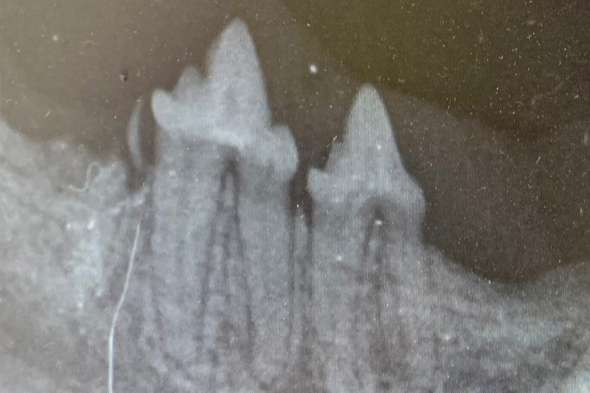

Wir sind besonders stolz Ihnen und Ihren Tieren ein hochauflösendes Zahnröntgen anbieten zu können. Denn nur die genaue Aufnahme jedes einzelnen Zahns, inklusive der Zahnwurzel und des Kieferknochen, erlaubt uns eine genaue Diagnosestellung.

Die beim Tier häufigsten Erkrankungen der Zähne sind vor allem im Bereich unterhalb des Zahnfleisches zu finden, also von außen kaum oder nicht sichtbar.